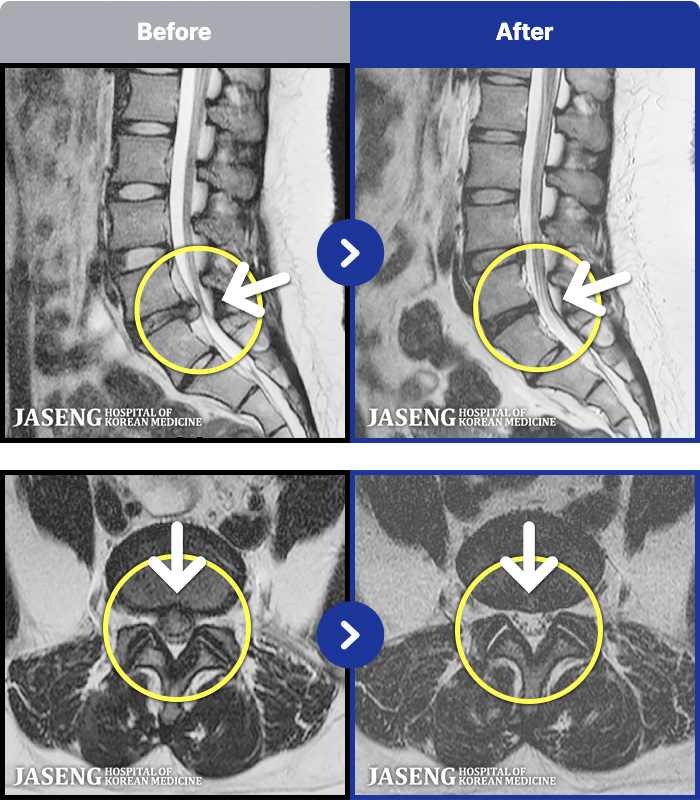

1,291 MRI ũ ʸ Ȯϼ.

[] 03.04.01~09.11.01